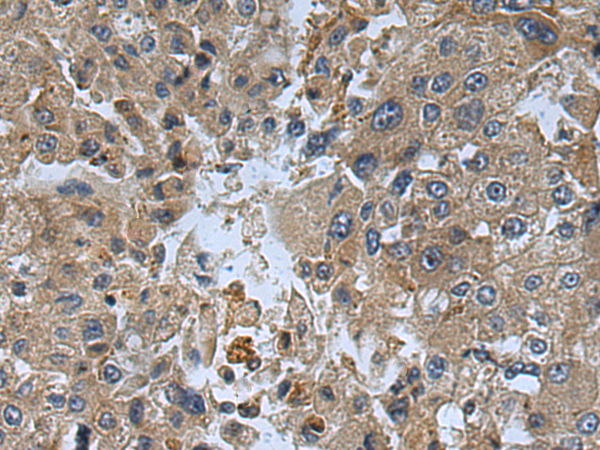

分类: 科研抗体货号: P08928别名: JTK1; IMD35应用: IHC反应种属: Human, Mouse